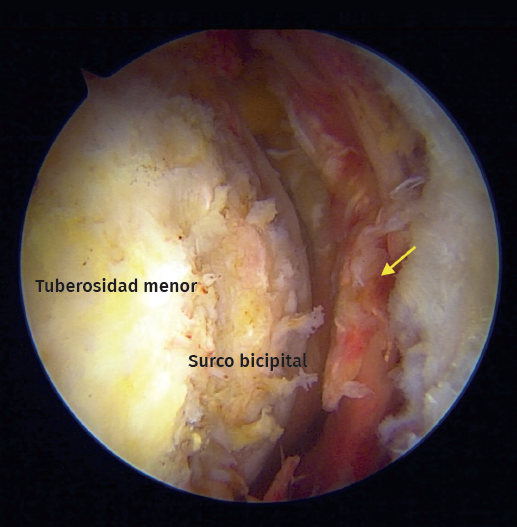

Durante el periodo descrito, se intervino a un total de 15 pacientes que cumplían con los criterios de inclusión. Se excluyó a un paciente debido a que el tiempo de seguimiento era insuficiente. Se incluyeron un total de 14 pacientes (Tabla 1), con una edad promedio de 65 años (rango de 46 a 76 años), 8 de los cuales eran hombres (57%). El tiempo promedio de seguimiento fue de 29,4 meses (rango de 24 a 41 meses). De los 14 pacientes evaluados, 13 (92,8%) presentaban algún compromiso del bíceps proximal como roturas parciales, lesiones degenerativas o inestabilidad medial (Figura 5). Se realizó una tenotomía del bíceps en 9 pacientes (64,2%), una tenodesis intraarticular en 2 casos (14,2%) y se detectó una rotura crónica del bíceps en 2 pacientes (14,2%). En la mitad de los pacientes (7) la rotura subescapular se reparó con 2 anclajes con nudo y en los restantes, con una fijación híbrida utilizando un anclaje superior con nudo y un anclaje inferior sin nudo con cintas de sutura (Tabla 2).

Figura 5. Vista artroscópica. Rotura completa del subescapular con inestabilidad medial de la cabeza larga del tendón del bíceps. Asterisco: tendón del bíceps. Flecha: rotura del tendón subescapular.